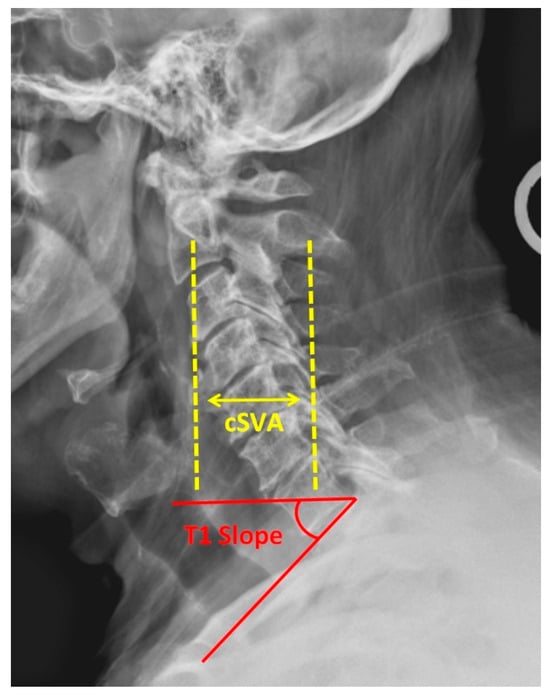

4. Sagittal Parameters

- Virk, S.; Lafage, R.; Elysee, J.; Louie, P.; Kim, H.J.; Albert, T.; Lenke, L.G.; Schwab, F.; Lafage, V. The 3 Sagittal Morphotypes That Define the Normal Cervical Spine: A Systematic Review of the Literature and an Analysis of Asymptomatic Volunteers. J. Bone Jt. Surg. Am. 2020, 102, e109. [Google Scholar] [CrossRef]

- Ling, F.P.; Chevillotte, T.; Leglise, A.; Thompson, W.; Bouthors, C.; Le Huec, J.C. Which parameters are relevant in sagittal balance analysis of the cervical spine? A literature review. Eur. Spine J. 2018, 27, 8–15. [Google Scholar] [CrossRef]

- Azimi, P.; Yazdanian, T.; Benzel, E.C.; Hai, Y.; Montazeri, A. Sagittal balance of the cervical spine: A systematic review and meta-analysis. Eur. Spine J. 2021, 30, 1411–1439. [Google Scholar] [CrossRef]